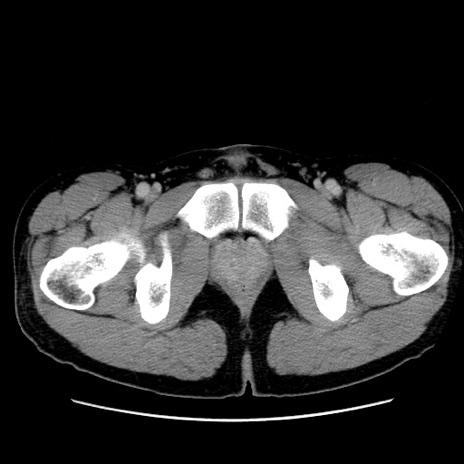

症例36(横断像)

【症例】20歳代 男性

【主訴】心窩部痛

【現病歴】今朝より上腹部痛あり。一旦軽快していたが再度出現したため救急要請。昨日夕に白身の魚を含む刺身を食べた。

【身体所見】BP 136/89mmHg、HR 74/min、BT 37.0℃、腹部:膨満、軟、心窩部に圧痛あり。反跳痛なし、筋性防御なし、腸雑音やや亢進あり。

【データ】WBC 17700、CRP 0.48